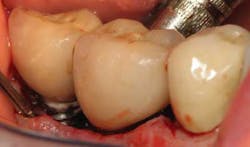

Fig. 2: Clinical probing showing suppuration around the implant-supported crown.

Fig. 4: Probing around implant-supported crown reveals depth and suppuration.